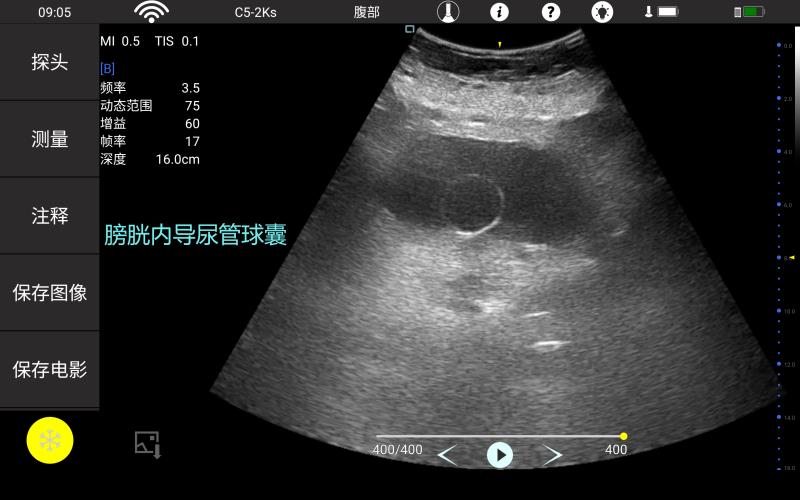

妇产科

泌尿科

• 大凸

腹部

肾脏